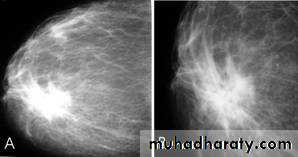

Fibroadenoma is a common benign breast lesion and results from excess proliferation of connective tissue. Fibroadenomas characteristically contain both stromal and epithelial cells.Mammography

Fibroadenomas have a spectrum of features from the well circumscribed discrete oval mass hypo- or isodense to the breast glandular tissue, to a mass with macrolobulation or partially obscured margin. Involuting fibroadenomas in older, typically postmenopausal patients may contain calcification, often producing the classic, coarse popcorn calcification appearance.